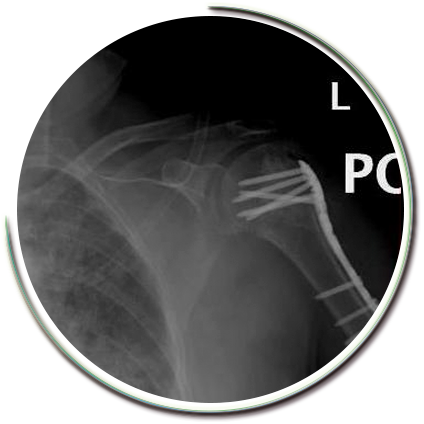

Parçalı kırıklarda kaynama sorunları ve işlev kaybı oluşmaması amacıyla sınırlı girişimsel cerrahi müdahale gerekebilmektedir. Kırık parçaları için çok kıymetli olan kanlanma bozulmadan (travmanın kendisi kanlanmayı yeterince etkileyebilir) kırık tespiti güçlü bir şekilde yapılabilmektedir. Kırık düzeltilmesi, açılan kas pencerelerinden yapılır. Parçaların tamamına hakim olabilmek amacıyla dikişler ve kilitli vidalı plaklar kullanılır. Kullanılan pencereler yerleştirilen plaklara göre oldukça küçük boyutlardadır. Pencerelerin bölgeden geçen sinirlere uygun mesafede olması gerekir.

Tespit gücü yüksek implantlar sayesinde birkaç hafta içerisinde, hastalar günlük hareketlerini sağlayabilecek ve kişisel ihtiyaçlarını giderebilecek hale gelebilmektedir. Böylece erken rehabilitasyon ve normal hayata hızlı bir dönüş sağlanabilmektedir..